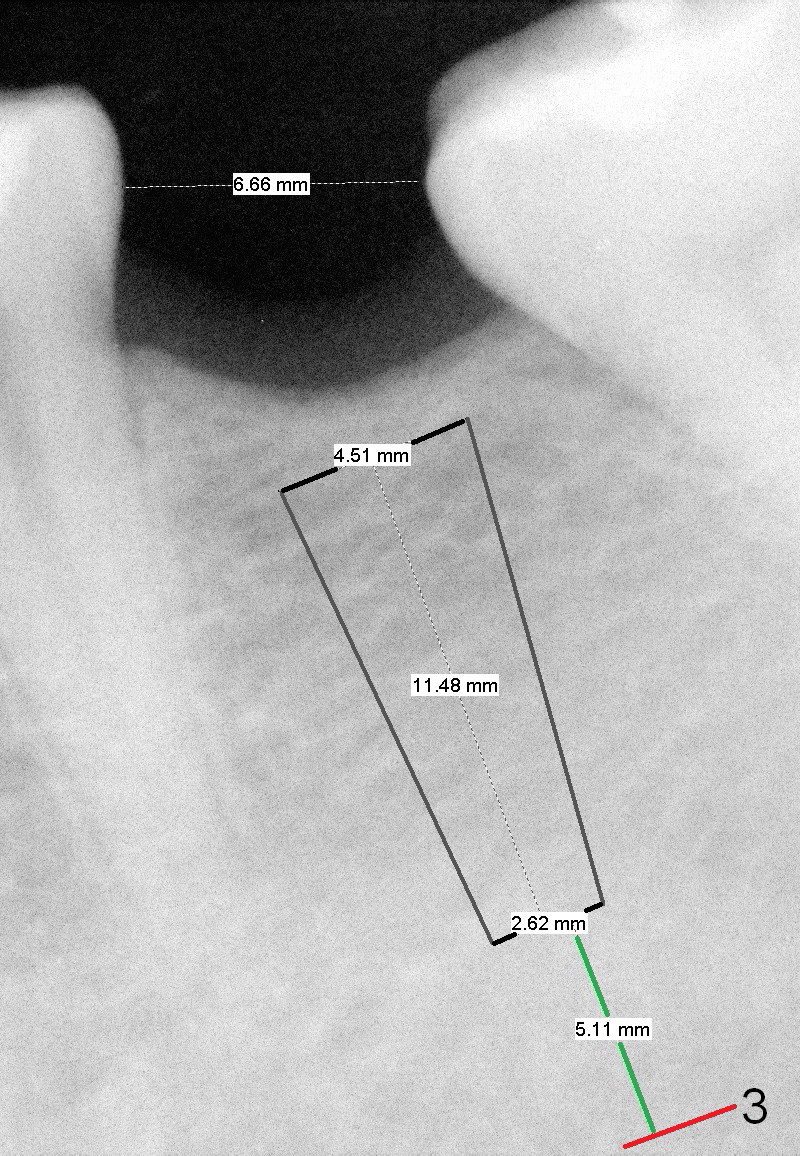

A 31-year-old woman agrees to have implant at #19 (Fig.1) after redoing MOL composite at #20 (Fig.2 *). The edentulous mesiodistal space is narrow (~ 6 mm in Fig.3). If the buccolingual bone width is found to be good after incision, a large implant is preferred. To gain space mesiodistally, the proximal surfaces of the neighboring teeth will be reduced (Fig.2 blue curved lines).